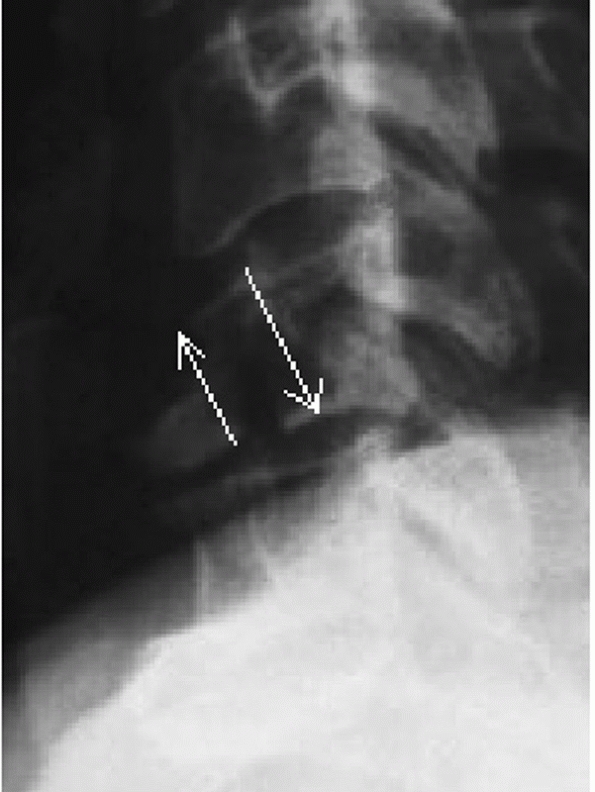

types, angulation following hangman’s fractures is not measured at the

fracture site. Instead, angulation between the C2 and C3 vertebral

bodies is assessed. Two method have been described.35 In the endplate method, the angle between lines drawn along the inferior endplates of C2 and C3 is measured (Fig. 42-6).

In the posterior tangent method, the angle of intersection between

lines drawn along the posterior vertebral bodies of C2 and C3 is

measured (Fig. 42-7). Translation of C2 on C3 can be measured using posterior vertebral body tangent lines as described below for subaxial levels.